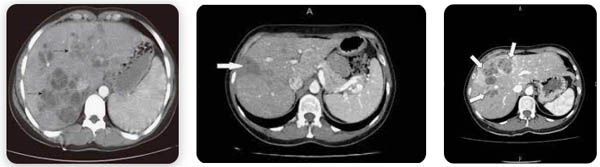

Hình 4. Hình ảnh tổn thương đa ổ abces do sán lá gan lớn trên cùng một bệnh nhân

Hình 5. Hình ảnh tổn thương đa ổ abces xen kẻ một ổ lớn do sán lá gan lớn

Hình 6. Hình ảnh tổn thương đa ổ abces do sán lá gan lớn cạnh các tạng khác

Trong các nghiên cứu mở rộng đa trung tâm về bệnh SLGL cho thấy chẩn đoán hình ảnh học đề cập đến nhu mô gan (pha cấp của ấu trùng sán khi xâm nhập vào nhu mô gan), CT-scaner giúp chỉ ra các vùng thương tổn chùm dưới bao gan và tính chất giảm âm. Trong khi đó chụp cộng hưởng từ (MRI) cũng cho các hình ảnh tương tự như trong CT-scanner nhưng hình ảnh rõ nét và đặc trưng hơn rất nhiều, giúp xác định và mô tả tổn thương đầy đủ hơn.

Một vài nghiên cứu trên thế giới cho thấytrên siêu âm và CT scanner có tổn thương đa ổ, mật độ giảm với sự tập trung các bóng mờ hình cục ở thuỳ gan (P) và dãn rộng các nhánh đường mật trong gan, nhất là thuỳ (P). Một số nhánh đường mật dãn có hang, kích thước trung bình. Đường mật bị bao quanh bởi một phần giảm mật độ làm thành từng ổ. Những điều tìm thấy này là biểu hiện của tắc nghẽn đường mật do biến chứng viêm đường mật, khi đó sẽ tạo thành các ổ hoại tử trong gan do quá trình tắc nghẽn này.

Ngoài ra, với sự trợ giúp của CT-scanner và MRI sẽ giúp thầy thuốc lâm sàng phân biệt hình ảnh giữa sán lá gan lớn Fasciola sp. với các khối thương tổn ác tínhở hệ gan mật khác. Điểm đặc biệt, trên siêu âm thường chúng ta thấy hình ảnh tổn thương trên gan mật thì với bờ viền ngoài không rõ ràng, song trên hình ảnh CT-scan hay MRI lại rất rõ ràng và tạo khối tách biệt so với nhu mô lành.